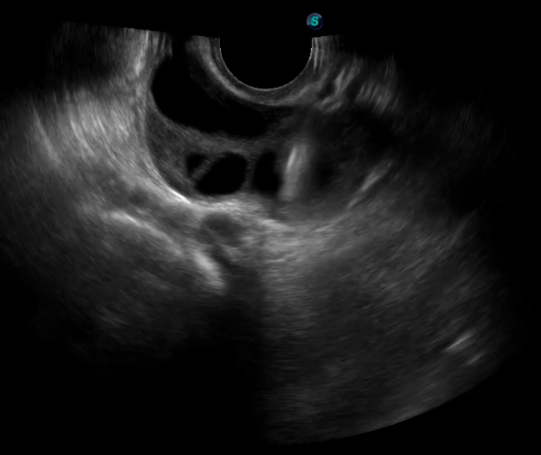

1生殖專(zhuān)用探頭

傳統(tǒng)腔內(nèi)探頭采用直柄設(shè)計(jì),在搭配穿刺架使用時(shí),手術(shù)空間小,不易操作;生殖專(zhuān)用的曲柄探頭,探頭柄采用彎曲成角度設(shè)計(jì),可實(shí)現(xiàn)監(jiān)視、取卵兩不誤,搭載穿刺架時(shí),可以清晰顯示穿刺針的進(jìn)針過(guò)程、深度和位置,實(shí)時(shí)監(jiān)視取卵全過(guò)程,保障取卵操作精準(zhǔn)與安全。

取卵臨床圖